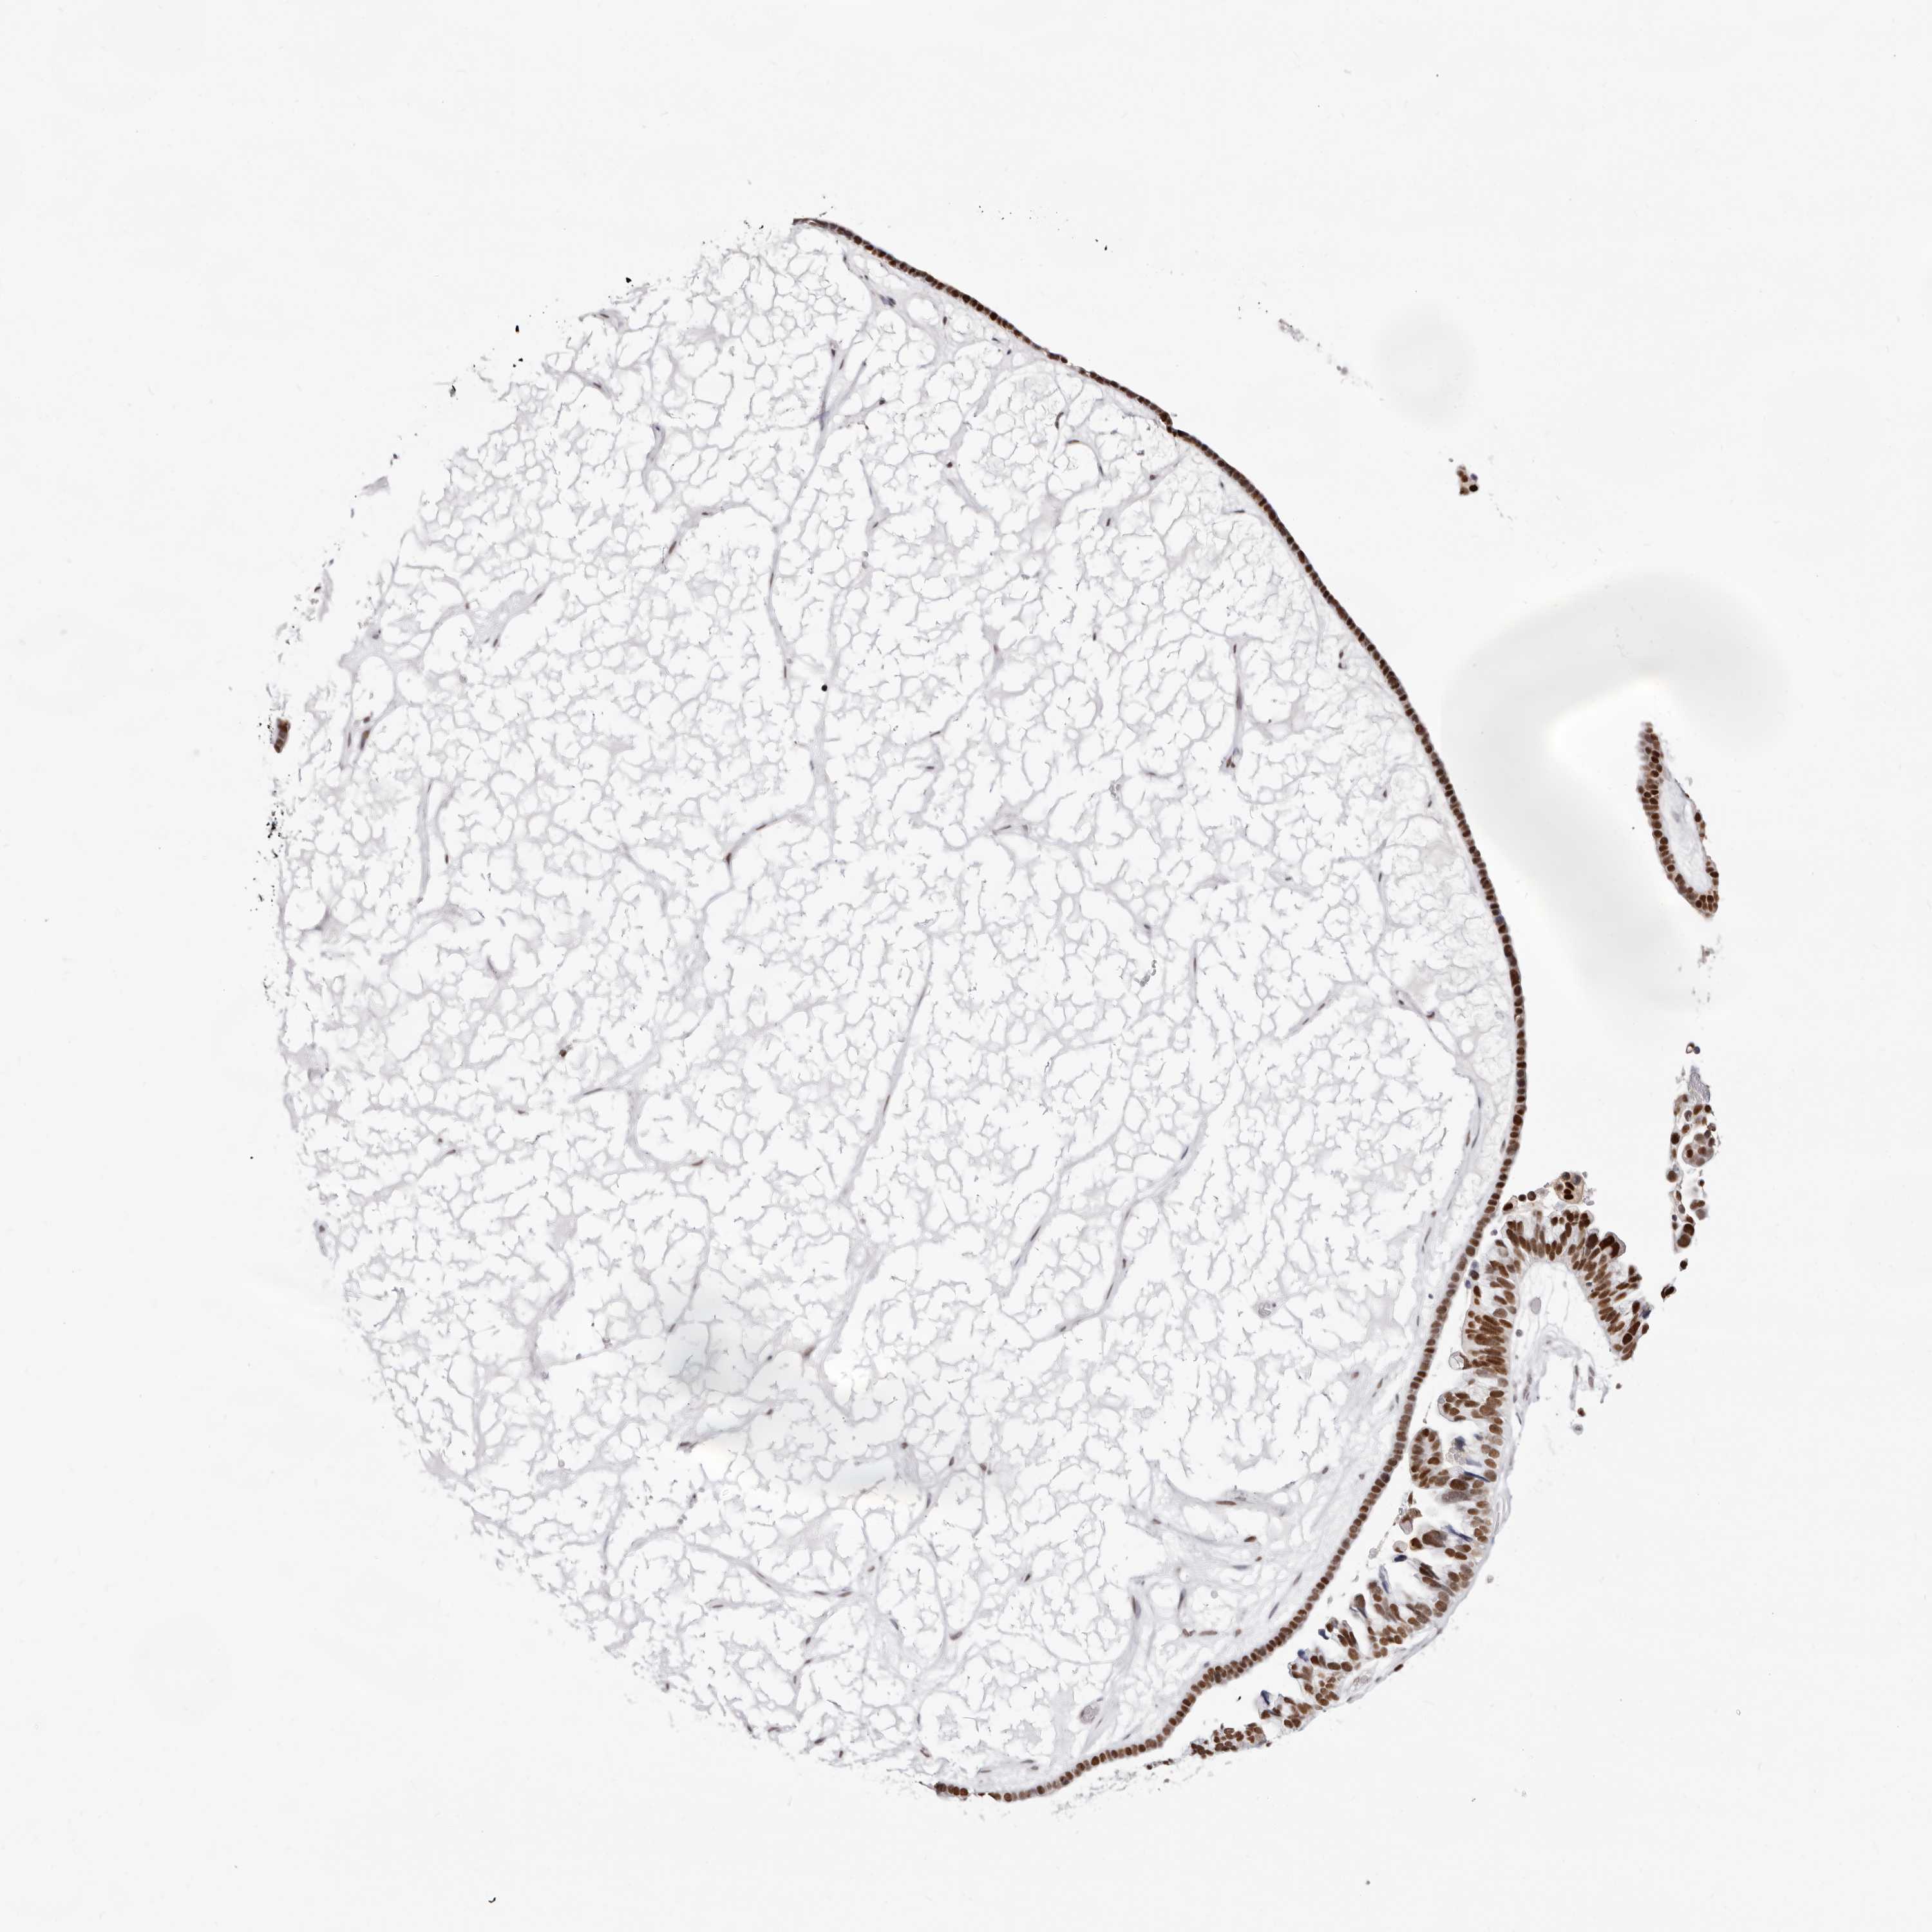

OVARIAN CANCER - Protein expressioni

A mouse-over function shows sample information and annotation data. Click on an image to view it in a full screen mode. Samples can be filtered based on level of antibody staining by selecting one or several of the following categories: high, medium, low and not detected. The assay and annotation is described here.

Note that samples used for immunohistochemistry by the Human Protein Atlas do not correspond to samples in the TCGA dataset.

Antibody stainingi

Antibody staining in the annotated cell types in the current human tissue is reported as not detected, low, medium, or high, based on conventional immunohistochemistry profiling in selected tissues. This score is based on the combination of the staining intensity and fraction of stained cells.

Each image is clickable and will lead to virtual microscopy that enables deeper exploration of all samples and also displays staining intensity scores, fraction scores and subcellular localization as well as patient and tissue information for each sample.

Antibody HPA029480

Antibody HPA029481

Cystadenocarcinoma, serous, NOS

Carcinoma, endometroid

Cystadenocarcinoma, mucinous, NOS

Carcinoma, NOS